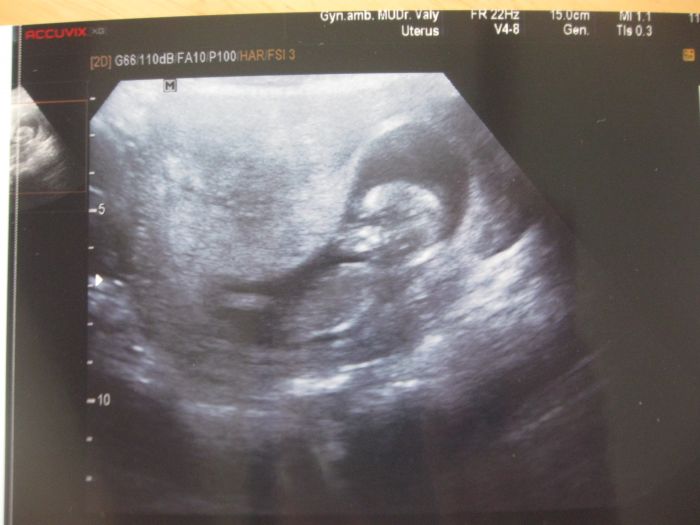

Jinak kontrola dopadla dobře dokonce mi dělala UTZ, prý ho dělá pokaždé mám i foto

dáváte ten UTZ, tak já tu mám jeden z 11+6 tak se taky pochlubím :)